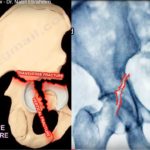

Transverse fractures of the Acetabulum

Courtesy: Prof Nabil Ebraheim, University of Toledo, Ohio, USA